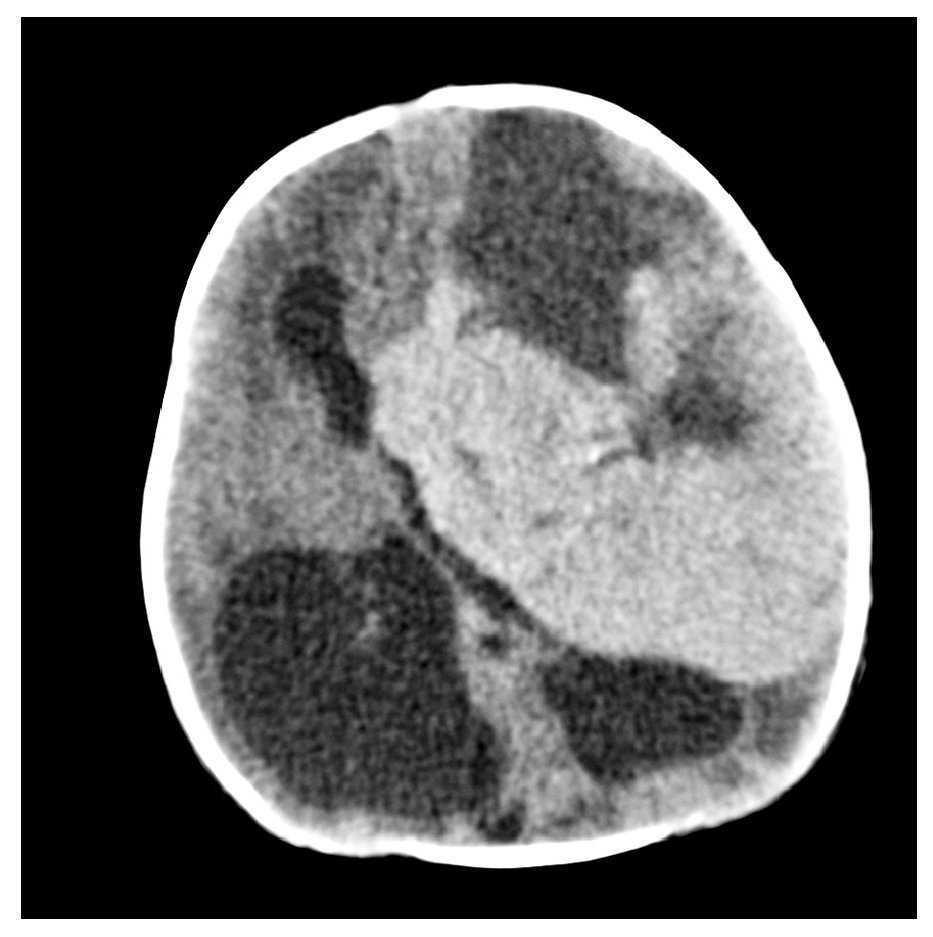

Gestante en el séptimo mes del embarazo. En ecografía de control se detecta hidrocefalia.

Fig. 2.